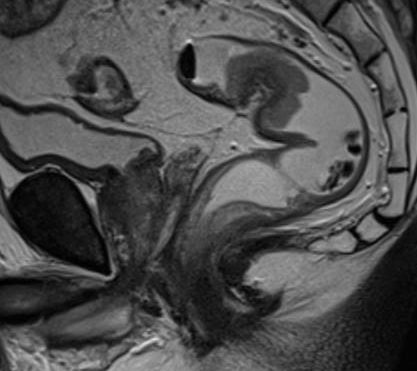

A correct preoperative stadialization of rectal carcinoma has a direct influence upon its therapeutic strategy, resulting in a significant improvement of the survival rate and life quality after the treatment. The therapeutic strategy refers to the option of undergoing or not preoperative radiochemotherapy before the total mesorectal excision (TME). The technical advances in the magnetic resonance domain makes possible the multiparametric examinations (mp MRI) with medical equipments (3T models are common) good enough to obtain images having an excellent quality, which allow a correct diagnosis of the local tumour spread. These multiparametric examinations include T2 multiplan sequences and T1 sequences, which offer valuable morphological information due to the high resolution of anatomic structures and DWI functional sequences, with a decisive role in tracing residual tumours after post-surgery radiochemotherapy. The functional examination using DWI is the only highly accurate non-invasive diagnostic method which can differentiate the fibrosis from vital tumoral remnants. The dynamic contrast-enhanced examination (DCE) combined with DWI and volumetry can give supplementary information as to the complete and incomplete response to RCT, and is efficient in detecting a local recurrence after TME. Also, MRI is the only diagnostic method which has the necessary accuracy to assess the meso-rectal fascia, which represents the circumferential resection margin (CRM) in the case of TME. With the help of MRI we can measure with a precision similar to histology the minimal distance to the mesorectal fascia, essential in planning the surgical treatment, and more important than the T stadialization. This allows the selection of patients with an unfavourable prognosis factor who would benefit from radiotherapy or from RCT. The evaluation of other prognostic factors as the condition of nodes, their number and primary site, and the extramural venous invasion (EMVI) have an important role in the individualized therapy.